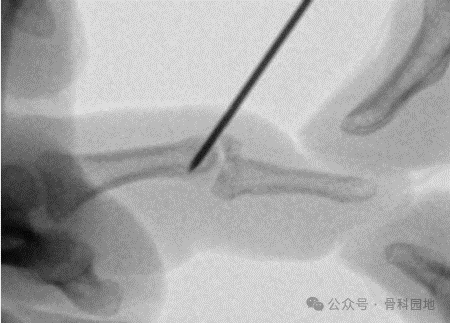

有一部分病人由于软组织和早期骨痂的形成填补了骨折间隙,复位时,将远端指骨推向腹侧,使关节处于掌侧半脱位(下图),复位不理想。

为了解决这个特定的问题,我们建议进行复位和固定时,类似于Ishiguro技术,但颠倒复位固定顺序,来解决这一问题(如下图)。